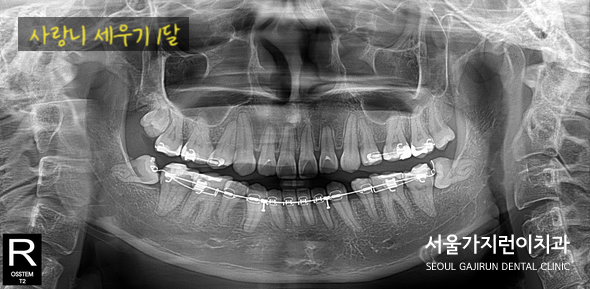

그렇게 사랑니 세우는 치아교정 과정을 보시면,

1달째와 13달때 차이가 확연히 나는 것을 볼 수 있는데요. 사랑니의 뿌리와 모양이 온전하다면 위와 같은 과정을 통해 사랑니를 세워 어금니로 사용할 수도 있겠습니다. 이후 교정이 완료된 모습은 바로 아래사진인데요.